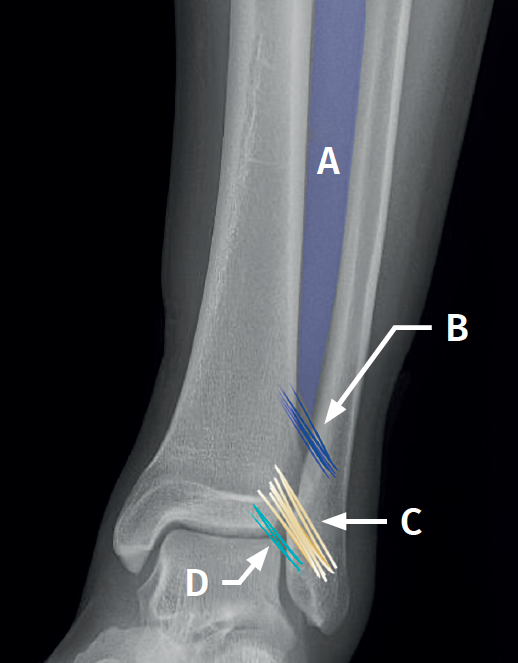

Syndesmosis (Figure 1)

The syndesmosis is a fibrous ring that joins the tibia and fibula distally(1). Its main function is to maintain the congruence of the tibiofibular mortise and to allow physiological micromovements of separation and rotation of the fibula with respect to the tibia(6).

- The anterior tibiofibular ligament (ATFL). Considered to be the first to be injured by external rotation or forced dorsiflexion forces. It extends obliquely from the anterior tubercle of the distal tibia, approximately 5 mm above the joint surface, to the anterior tubercle of the distal fibula, running proximal-medial to distal-lateral and crossing the anterolateral corner of the talus(7).

- The posterior tibiofibular ligament (PTFL), which is stronger than the anterior ligament. It extends from the posterior tibial malleolus to the posterior tubercle of the fibula and runs proximal-medial to distal-lateral. It forms an angle of 20º to40° with the horizontal plane.

- The interosseous ligament (IL), a distal thickening of the interosseous membrane that acts as a "spring" or dynamic stabilizer.

- The transverse ligament, located in the most posterior part, and considered by some authors as the distal portion of the PTFL.

For definitive fixation, the surgical options range between rigid fixation with screws and dynamic fixation. Screws have been the standard procedure for decades, but involve complications, such as loosening or rupture. Furthermore, some surgeons advocate their removal, with the inherent risk of recurrence of instability(27). Dynamic fixation was designed to overcome some of these problems by allowing a degree of physiological movement of the syndesmosis, facilitating early weight bearing, reducing the risk of rupture, and eliminating the need to remove the implant (Figure 7B).

Grassi et al., in a meta-analysis involving over 300 patients, demonstrated an overall decrease in the relative risk of complications (RR = 0.55, p = 0.003) with dynamic systems(28). Raeder et al., in a randomized trial of 97 patients contrasting screw fixation versus a dynamic system, reported a lower incidence of osteoarthritis with suture buttons of 65% versus 35% (p = 0.009) at 5 years(29). Suture button constructions afford a degree of micro-mobility, mimicking physiological mobility, which can promote ligament healing. Likewise, flexible implants are better able to tolerate an imperfect reduction, as a possible complication, even if arthroscopic control of the joint is performed.